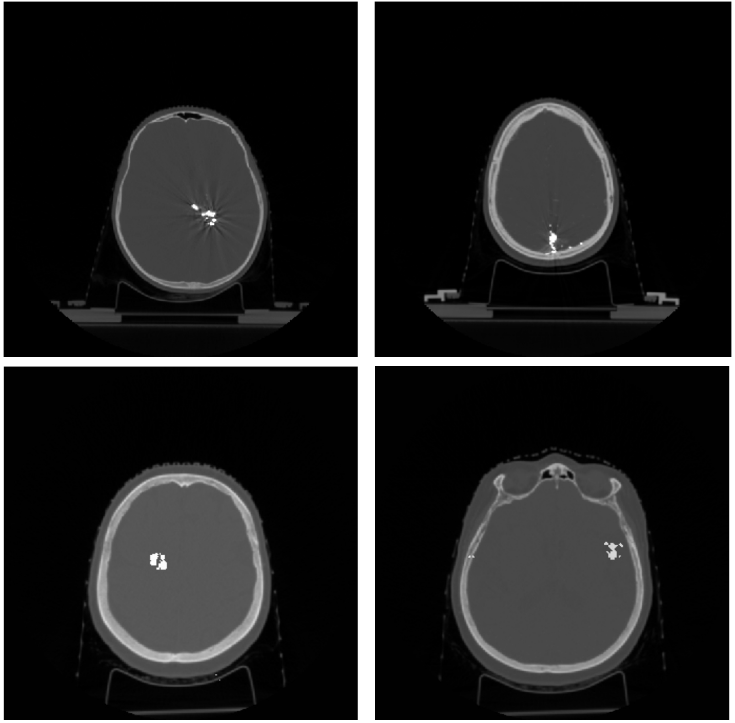

Refer to caption

Figure 2: Example of real shapes of high density objects (above) and shapes generated via proposed pipeline (below).

Figure 2 shows examples of real and generated objects. Using that algorithm for each CT image, we created 30 differently distributed object masks with an approximate depth of 90 slices per sample on average.